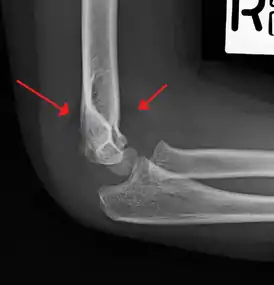

Supracondylar humerus fracture

| An elbow X-ray showing a displaced supracondylar fracture in a young child | |

X-rays

Diagnosis is confirmed by x-ray imaging. Antero-posterior (AP) and lateral view of the elbow joint should be obtained. Any other sites of pain, deformity, or tenderness should warrant an X-ray for that area too. X-ray of the forearm (AP and lateral) should also be obtained for because of the common association of supracondylar fractures with the fractures of the forearm. Ideally, splintage should be used to immobilise the elbow at 20 to 30 degrees flexion in order to prevent further injury of the blood vessels and nerves while doing X-rays. Splinting of fracture site with full flexion or extension of the elbow is not recommended as it can stretch the blood vessels and nerves over the bone fragments or can cause impingement of these structures into the fracture site.[2]